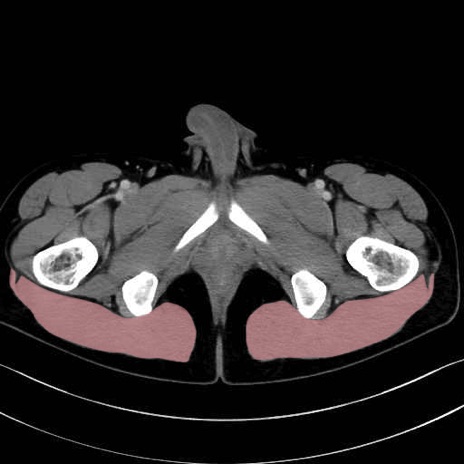

大殿筋 (Gluteus maximus)